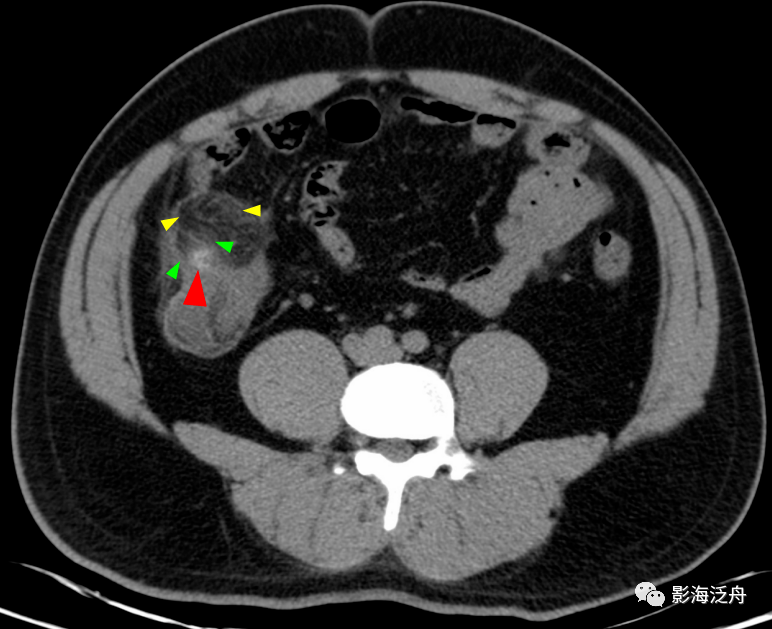

阑尾根部(黄箭)稍增粗,壁厚而强化,近端管腔内见高密度粪石影,注意

盲肠憩室内环形粪干(红箭),憩室周围无渗出;盲肠憩室内结节状粪石